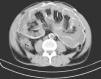

AssessmentThe Kt/V peritoneal was low and peritoneal equilibration test was of a high transporter. At admittance, the physical examination revealed diffuse abdominal pain without peritoneal irritation signs. The effluent had three white bloodcells/mm3, and cultures of dialysate showed no growth of bacteria or fungi. He had anemia and CD4 count was above 400mm–3. An abdominal radiograph showed marked peritoneal fibrosis outlining bowel loops (Fig. 1). A computed tomographic scan of the abdomen confirmed thickening of the peritoneum without intestinal obstruction (Fig. 2).